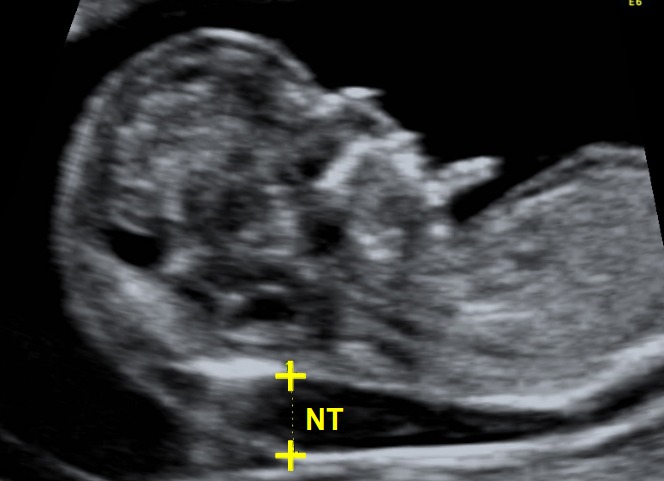

Aneuploidy/ Nuchal Translucency(NT) scan

Nuchal translucency scan is done around the 11th to 14th week of pregnancy. The scan aims to measure the size of the nuchal fold at the back of the baby’s neck to rule out the possibility or risk of any chromosomal abnormalities. With the help of a nuchal translucency scan, your health professional will rule out the risk of abnormalities like trisomy 21 (Down Syndrome), trisomy 18 (Edwards Syndrome), or trisomy 13 (Patau syndrome).